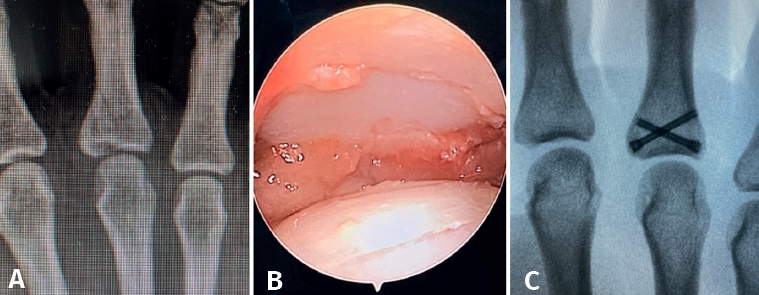

- Fractures with avulsion of the insertion of the collateral ligament (Figures 2 and 3).

- Intra-articular fractures proper, caused by compression or shear mechanisms.

Once the fragments have been reduced, 0.8 or 1.0 Kirschner wires are used to maintain reduction (Figure 7). Sometimes we can only maintain reduction by applying a stop, to prevent the osteochondral fragment from collapsing. Depending on the fracture pattern and the surgeon's preference, we can use conventional screws, cannulated screws, etc. (Figures 8 and 9).